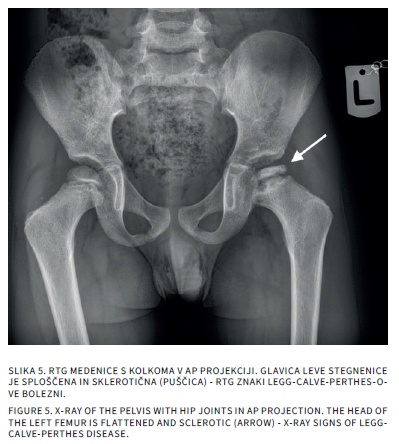

Bolečine v mišičnoskeletnem sistemu so v otroškem obdobju sorazmerno pogoste. Delimo jih na akutne in kronične, slednje trajajo več kot 3 mesece. Diferencialna diagnoza tako akutnih kot kroničnih bolečin v sklepih pri otrocih je široka. Slikovne preiskave so poleg anamneze, klinične slike in laboratorijskih izvidov pomembne v diagnostičnem postopku iskanja vzrokov bolečine. Katero slikovno metodo uporabimo najprej, je odvisno od mesta bolečine in od prizadetosti tkiva. Pri mehkotkivnih spremembah in oteklinah sklepov je prva diagnostična metoda ultrazvočna preiskava, pri sumu na prizadetost kosti pa rentgensko slikanje. Če je potrebno, sledi magnetnoresonančno slikanje ali računalniška tomografija. V prispevku bomo opisali anatomske in morfološke značilnosti otroškega skeleta, ki lahko dajejo videz patoloških sprememb ter slikovne diagnostične postopke pri akutnih in kroničnih bolečinah v sklepih.